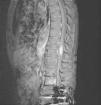

Los meningiomas son los tumores más frecuentes localizados a nivel espinal junto a neurinomas y metástasis. Estos tumores suelen ser intradurales y extramedular. Son pocos los casos descritos en la literatura con una localización puramente intramedular (menos de 10 casos) y frecuentemente se observan en la unión cráneo-cervical. Ante la presencia de un tumor intramedular, realizamos diagnósticos diferenciales con ependimomas, astrocitomas, etc. En este artículo presentamos el primer caso descrito en la literatura de un paciente con un meningioma tipo rabdoide exclusivamente intramedular a nivel del cono medular.

Meningiomas are the most frequent tumors located at the spinal level together with neurinomas and metastases. These tumors tend to be intradural and extramedullar. There are few cases described in the literature with a purely intramedullary location (less than 10 cases) and they are frequently observed in the union craneal-cervical. In the presence of an intramedullary tumor we perform differential diagnoses with ependymomas, astrocytomas... In this article we present the first case described in the literature of a patient with a rabdoid-type meningioma exclusively intramedullary at the level of the medullary cone.